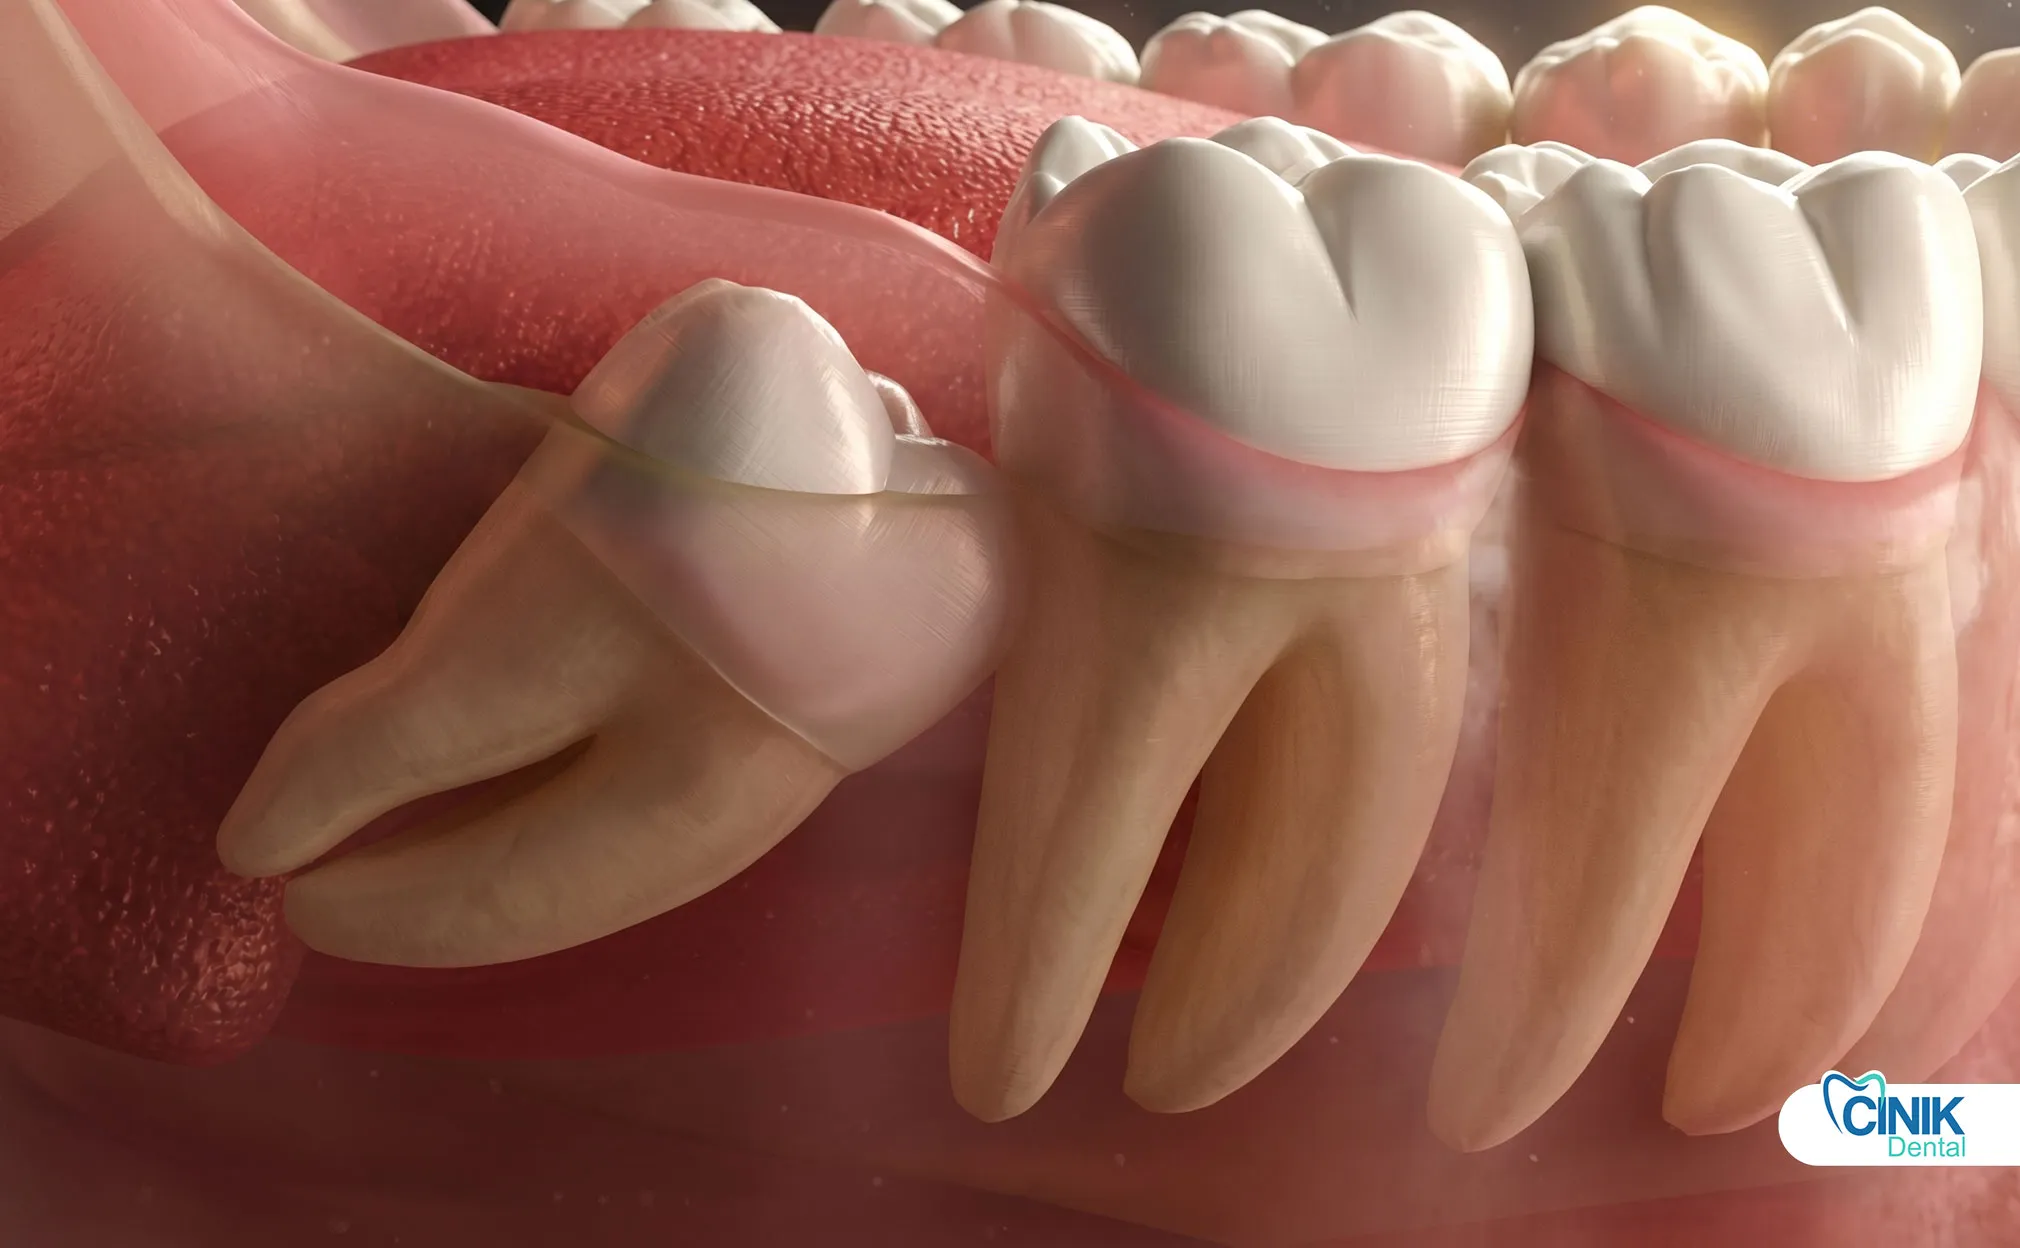

Impaction classifications follow specific angular relationships between the tooth and adjacent second molar:

Mesioangular | Crown angled toward front of mouth | 44% | Moderate |

Horizontal | Crown perpendicular to second molar | 3% | High |

Surgical extraction addresses impacted or partially erupted teeth requiring:

Mucoperiosteal flap elevation

Osteotomy (bone removal)

Tooth sectioning (odontectomy)

Suturing for wound closure